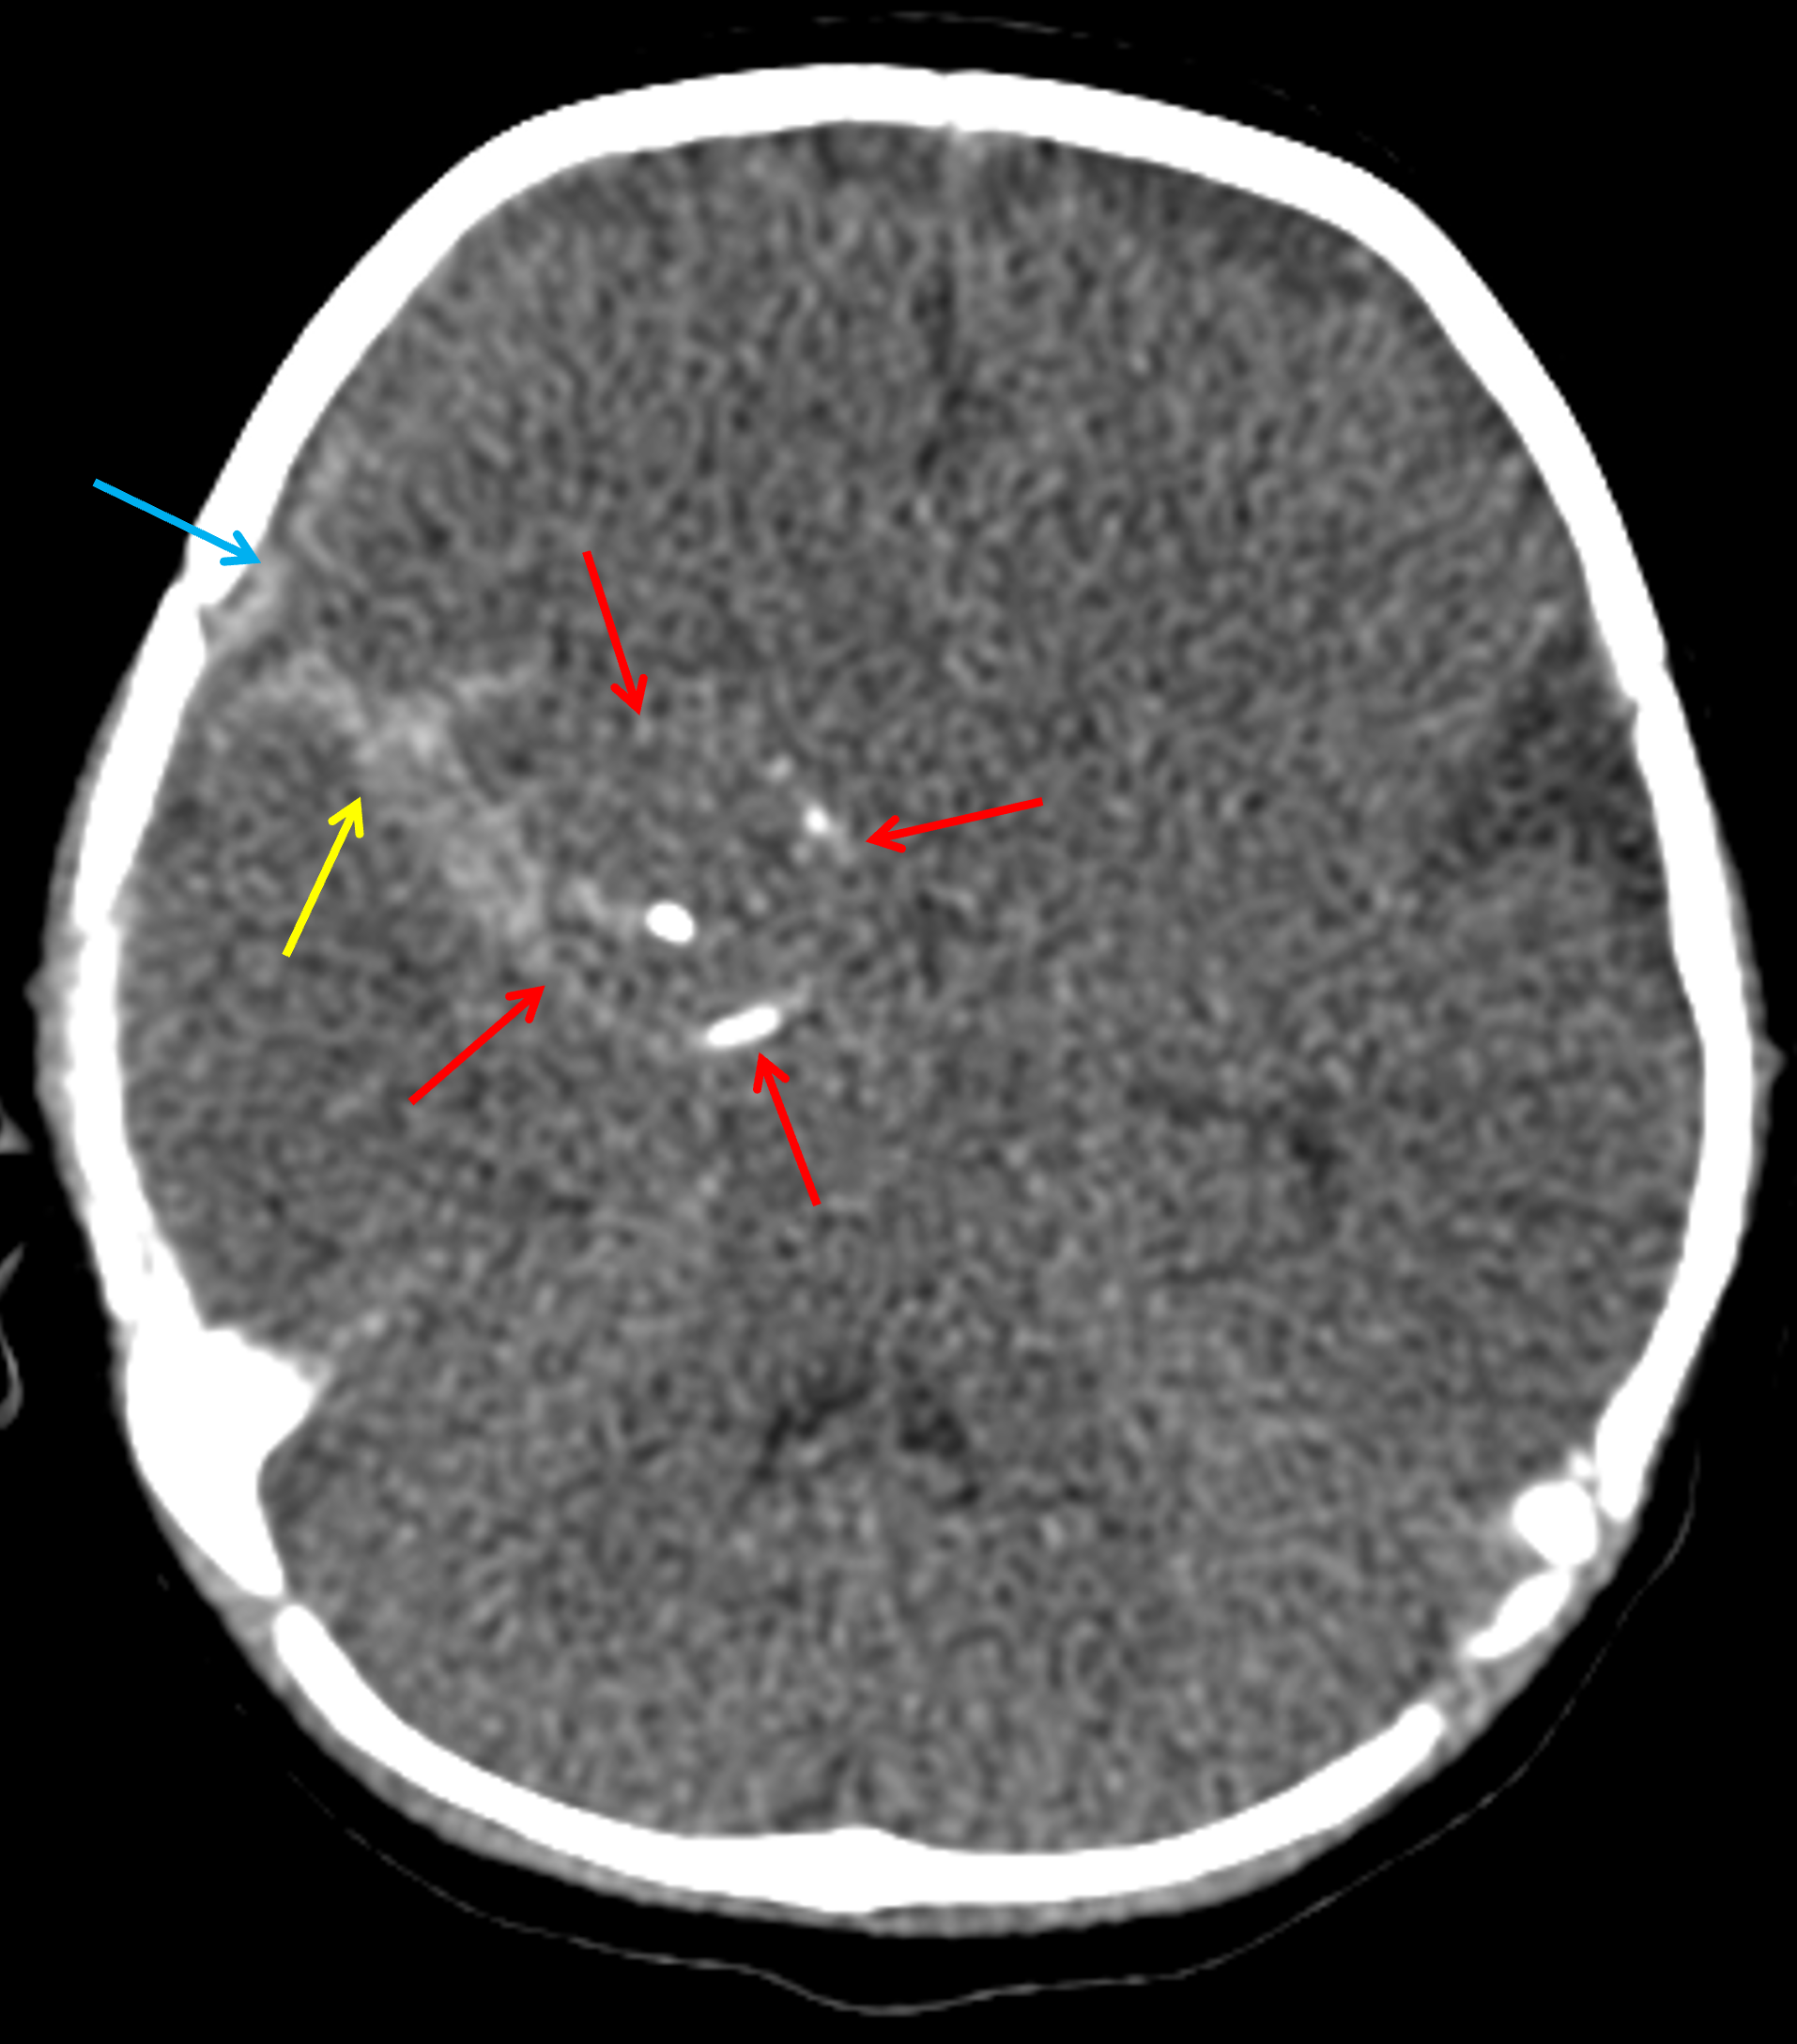

Age: 2 months

Sex: Female

Indication: Fussiness, bulging anterior fontanelle

CT

Giant cerebral aneurysm